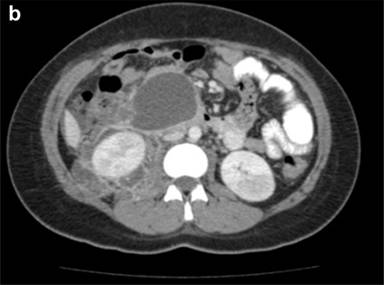

Endoscopic retrograde cholangiopancreatography (ERCP) is a fundamental tool in the management of in magnetic resonance cholangiopancreatography (MRCP) and endoscopic ultrasound (EUS), ERCP has biliary and pancreatic diseases. With technological advances evolved into a therapeutic rather than diagnostic procedure. Nevertheless, these procedures carry significant risk, with post-ERCP pancreatitis (PEP) being the most frequent and dreaded of these [1] (Figure 1). The incidence of pancreatitis after ERCP is approximately 5-10% [2-4], but exceeds 30% in certain high-risk groups [5]. It is essential for the modern advanced endoscopist to recognize PEP, understand the risk factors, measures for prevention, and the necessary steps in management. The primary aim of this article will be to review the recent advances in prevention and management of PEP.

Figure 1. Computed tomography reveals peri-pancreatic fluid and stranding two days after ERCP in 40-year-old man with severe epigastric pain and fevers. |